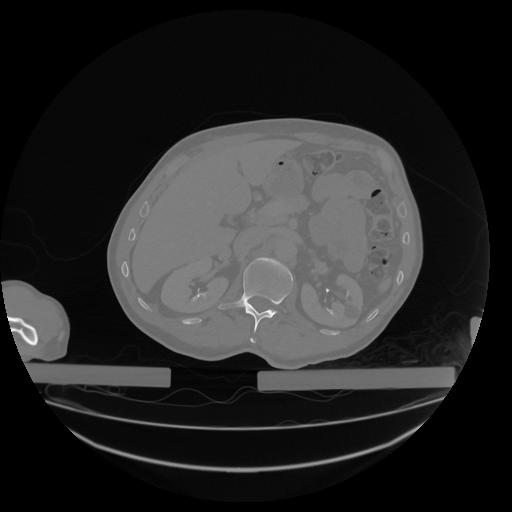

34 CUERPO,CE,Vol,1.0,CUERPO,,